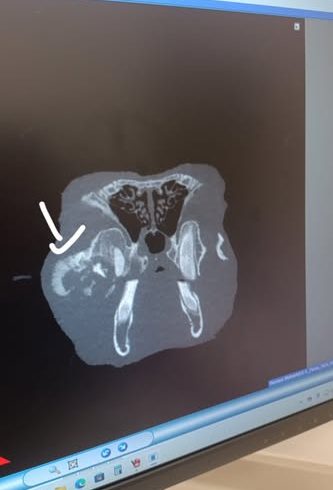

Vor einem Jahr kam sie zusammen mit ihrer Schwester zu uns. Ihre Schwester, die extrem klein war, ist bereits kurz darauf verstorben. Durch Inzucht hat auch Florea verschieden Baustellen. Sie ist kleinwüchsig, hat das Fell eines Babykaninchens und extreme Zahnfehlstellungen. Alle zwei Wochen mussten wir die Schneidezähne korrigieren, immer würde über einen OP zum Entfernen der Schneidezähne nachgedacht, aber sowohl wir als auch der Tierarzt hatten Bedenken wegen der Narkose. Vor 2 Monaten aber kamen wir um die OP nicht mehr herum und ihr wurden die oberen Schneidezähne sowie die oberen rechten Backenzähne entfernt. Sie hat die Narkose gut überstanden, hatte aber nach der Operation mit hartnäckigem Eiter zu kämpfen. Nach 4 Wochen war dann endlich alles gut verheilt. Nun kam vorletzte Woche der Eiter zurück und unser Tierarzt empfahl uns, ein Wach-CT machen zu lassen um zu sehen, was da los ist. Letzte Woche Montag war es dann soweit und die Ergebnisse sind niederschmetternd. Zwei ihrer oberen Backenzähne sind nachgewachsen, sie hat außerdem eine Verdichtung am rechten Jochbein, entweder durch eine starke Entzündung oder durch einen Tumor, dafür muss erst eine Probe entnommen werden. Auch die Nase ist auf Höhe des linken entfernten Schneidezahns verdichtet, auch hier muss nochmal aufgemacht werden. Die Ärztin ist in ihrer Prognose sehr vorsichtig und macht uns keine großen Hoffnungen. Auch unser Tierarzt sieht das so, er geht auch eher von einem Tumor aus, da sich Floreas Haut und Fell verändern. Nichtsdestotrotz wollen wir ihr eine Chance geben, der Termin für die zweite OP steht und danach wissen wir dann mehr. Sie wird nicht alt werden, aber ein bisschen Zeit hätte sie schon noch verdient!